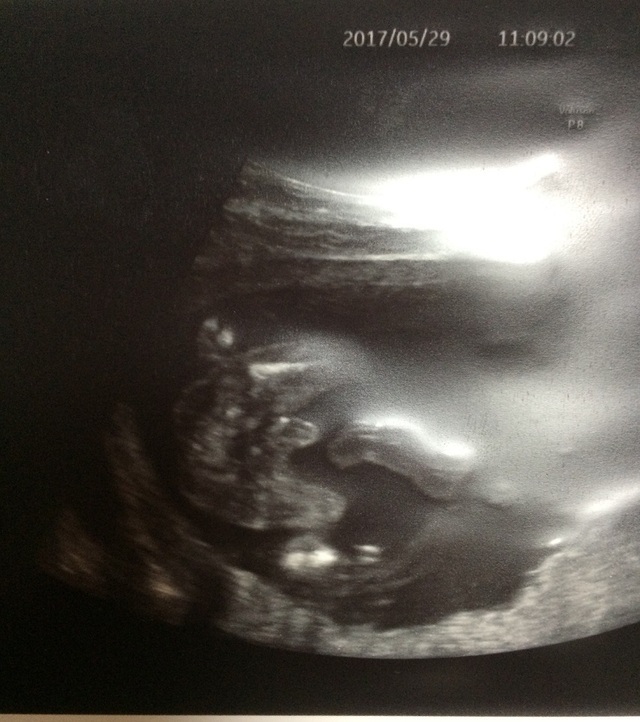

17週2日(17w2d・女の子)|osiosi さん(26歳)

エコー写真撮影時のエピソード:

絵に書いたようなエコー写真がとれて とても驚きました! ずっと逆子がなおらなくて、心配していましたがある日突然向きが変わったので良かったです。

この写真ではありませんが、 エコーで見ている時にあくびしているところを見られたので、そのエコー写真が運良く取れたら 面白かったのになーと思いました。(笑)